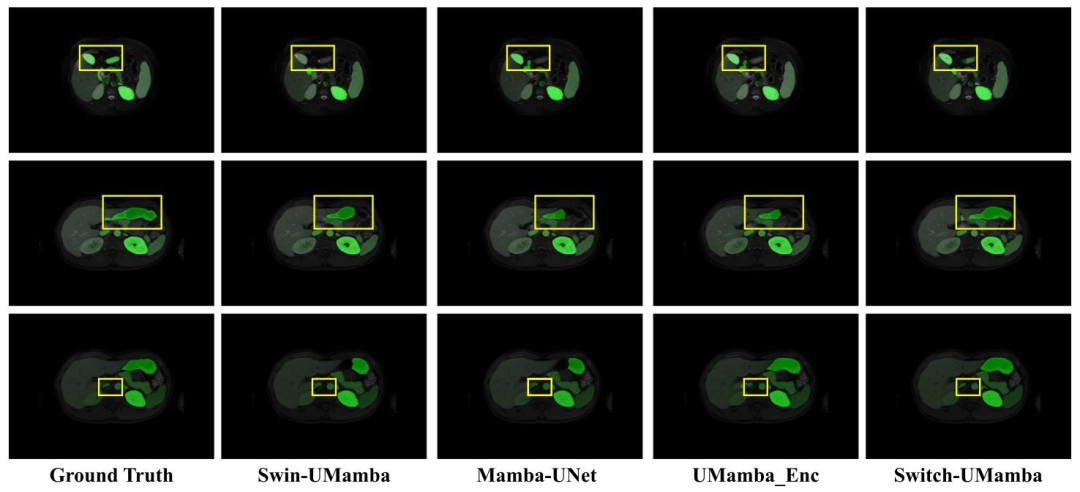

Fig. 5. Visualization of segmentation examples from the Abdominal MRI dataset. Switch-UMamba precisely discerns the morphology and classification of thesegmented anatomical structures

图5 腹部MRI数据集分割示例可视化 Switch-UMamba模型可精准识别被分割解剖结构的形态与类别。